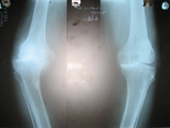

Arthritis both knees varus deformity pre op Post op Total Knee Replacement Post op Total Knee Replacement